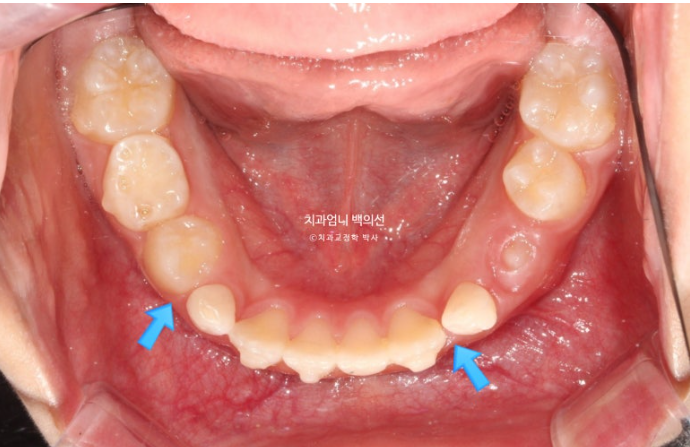

측절치와 송곳니날 자리가 부족해서 악궁확장도 필요한 상황입니다.

악궁확장으로 파란 화살표 반대교합이 해소가 되면서 교합간섭이 사라졌습니다.

아래 붙어있는 메탈 고리는 고무줄 거는 고리입니다.

악궁확장으로 넓어진 악궁 덕분에 공간이 좁아 못 나오던 측절치도 잘 나오고 있습니다.

아래턱의 위치는 잘 유지되고 있으며 이제 측절치가 충분히 나와 재제작에 들어갑니다.

측절치를 포함한 앞니는 잘 배열 되었습니다.

유치송곳니 벌어진 부분은 영구치 송곳니가 나올 때 공간이 부족하지 않도록 의도적으로 형성한 공간입니다.

영구치 맹출 공간은 충분하고 배열과 중심선 교합 모든 게 좋습니다.